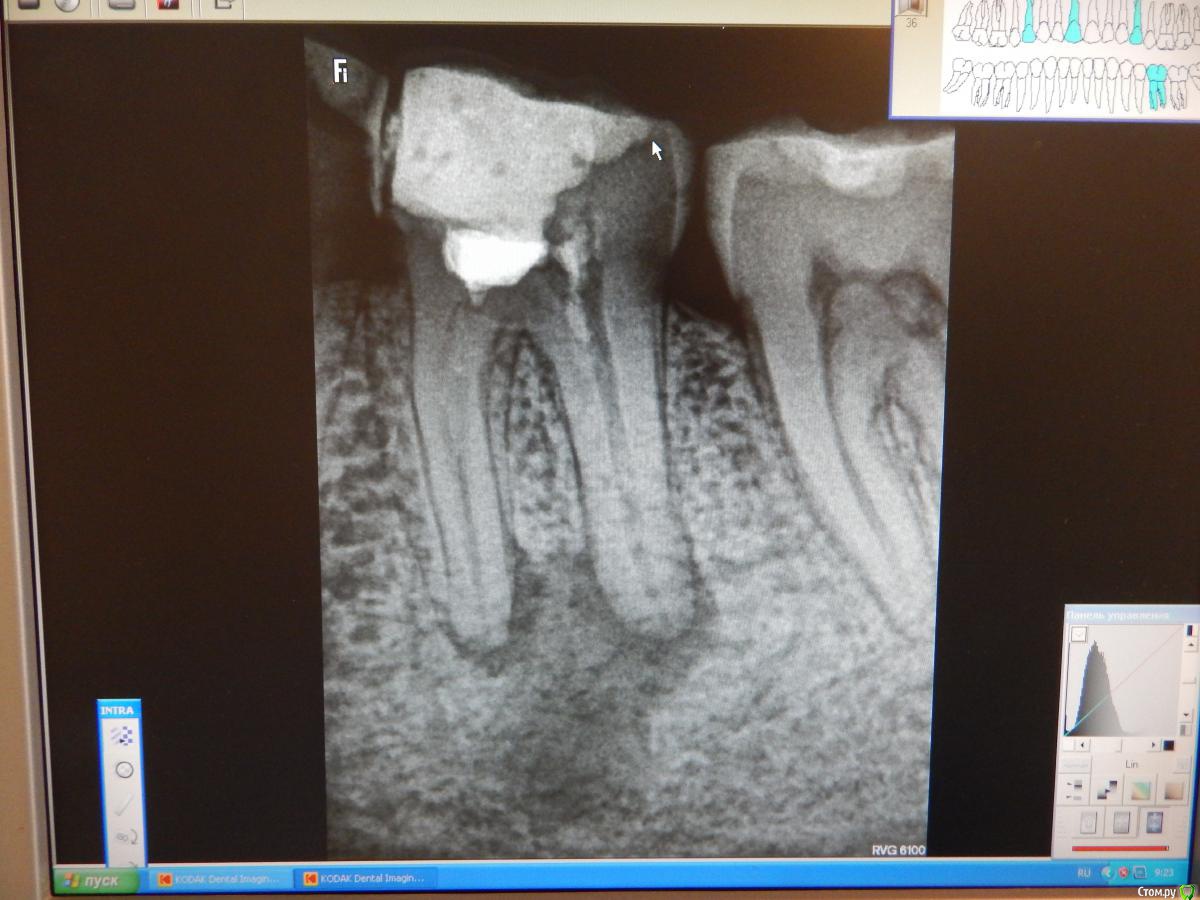

dantist_movani Опубликовано 8 октября, 2015 Поделиться Опубликовано 8 октября, 2015 Пациент обратился более 2 месяцев назад с жалобами на боли при накусывании, постоянные ноющие боли в зубе 3.6. Со слов больного зуб болел и ранее, но спасали НПВС, а тут 3 дня не может уснуть. Ранее зуб лечился (резорцин-формалиновый метод), перкуссия положительная, по переходной складке всё спокойно, лимфоузлы слева(поднижнечелюстные) чуть увеличены, при пальпации болезненны. Удалил, кюретаж, отделяемого никакого, под сгустком лунка зажила. Интраоральный снимок, делался в 2011 году, но зуб тогда болеть перестал. КТ на следующий день после удаления. Радикулярная киста? Какой план действий в данной ситуации? Ссылка на комментарий

diesel87 Опубликовано 8 октября, 2015 Поделиться Опубликовано 8 октября, 2015 Меня больше волнует как перегородка в воздухе висит.... 5 Ссылка на комментарий

voff Опубликовано 12 октября, 2015 Поделиться Опубликовано 12 октября, 2015 бывает, еще больше бывают "дырки". Тут одним имплантом не обойдешься Ссылка на комментарий